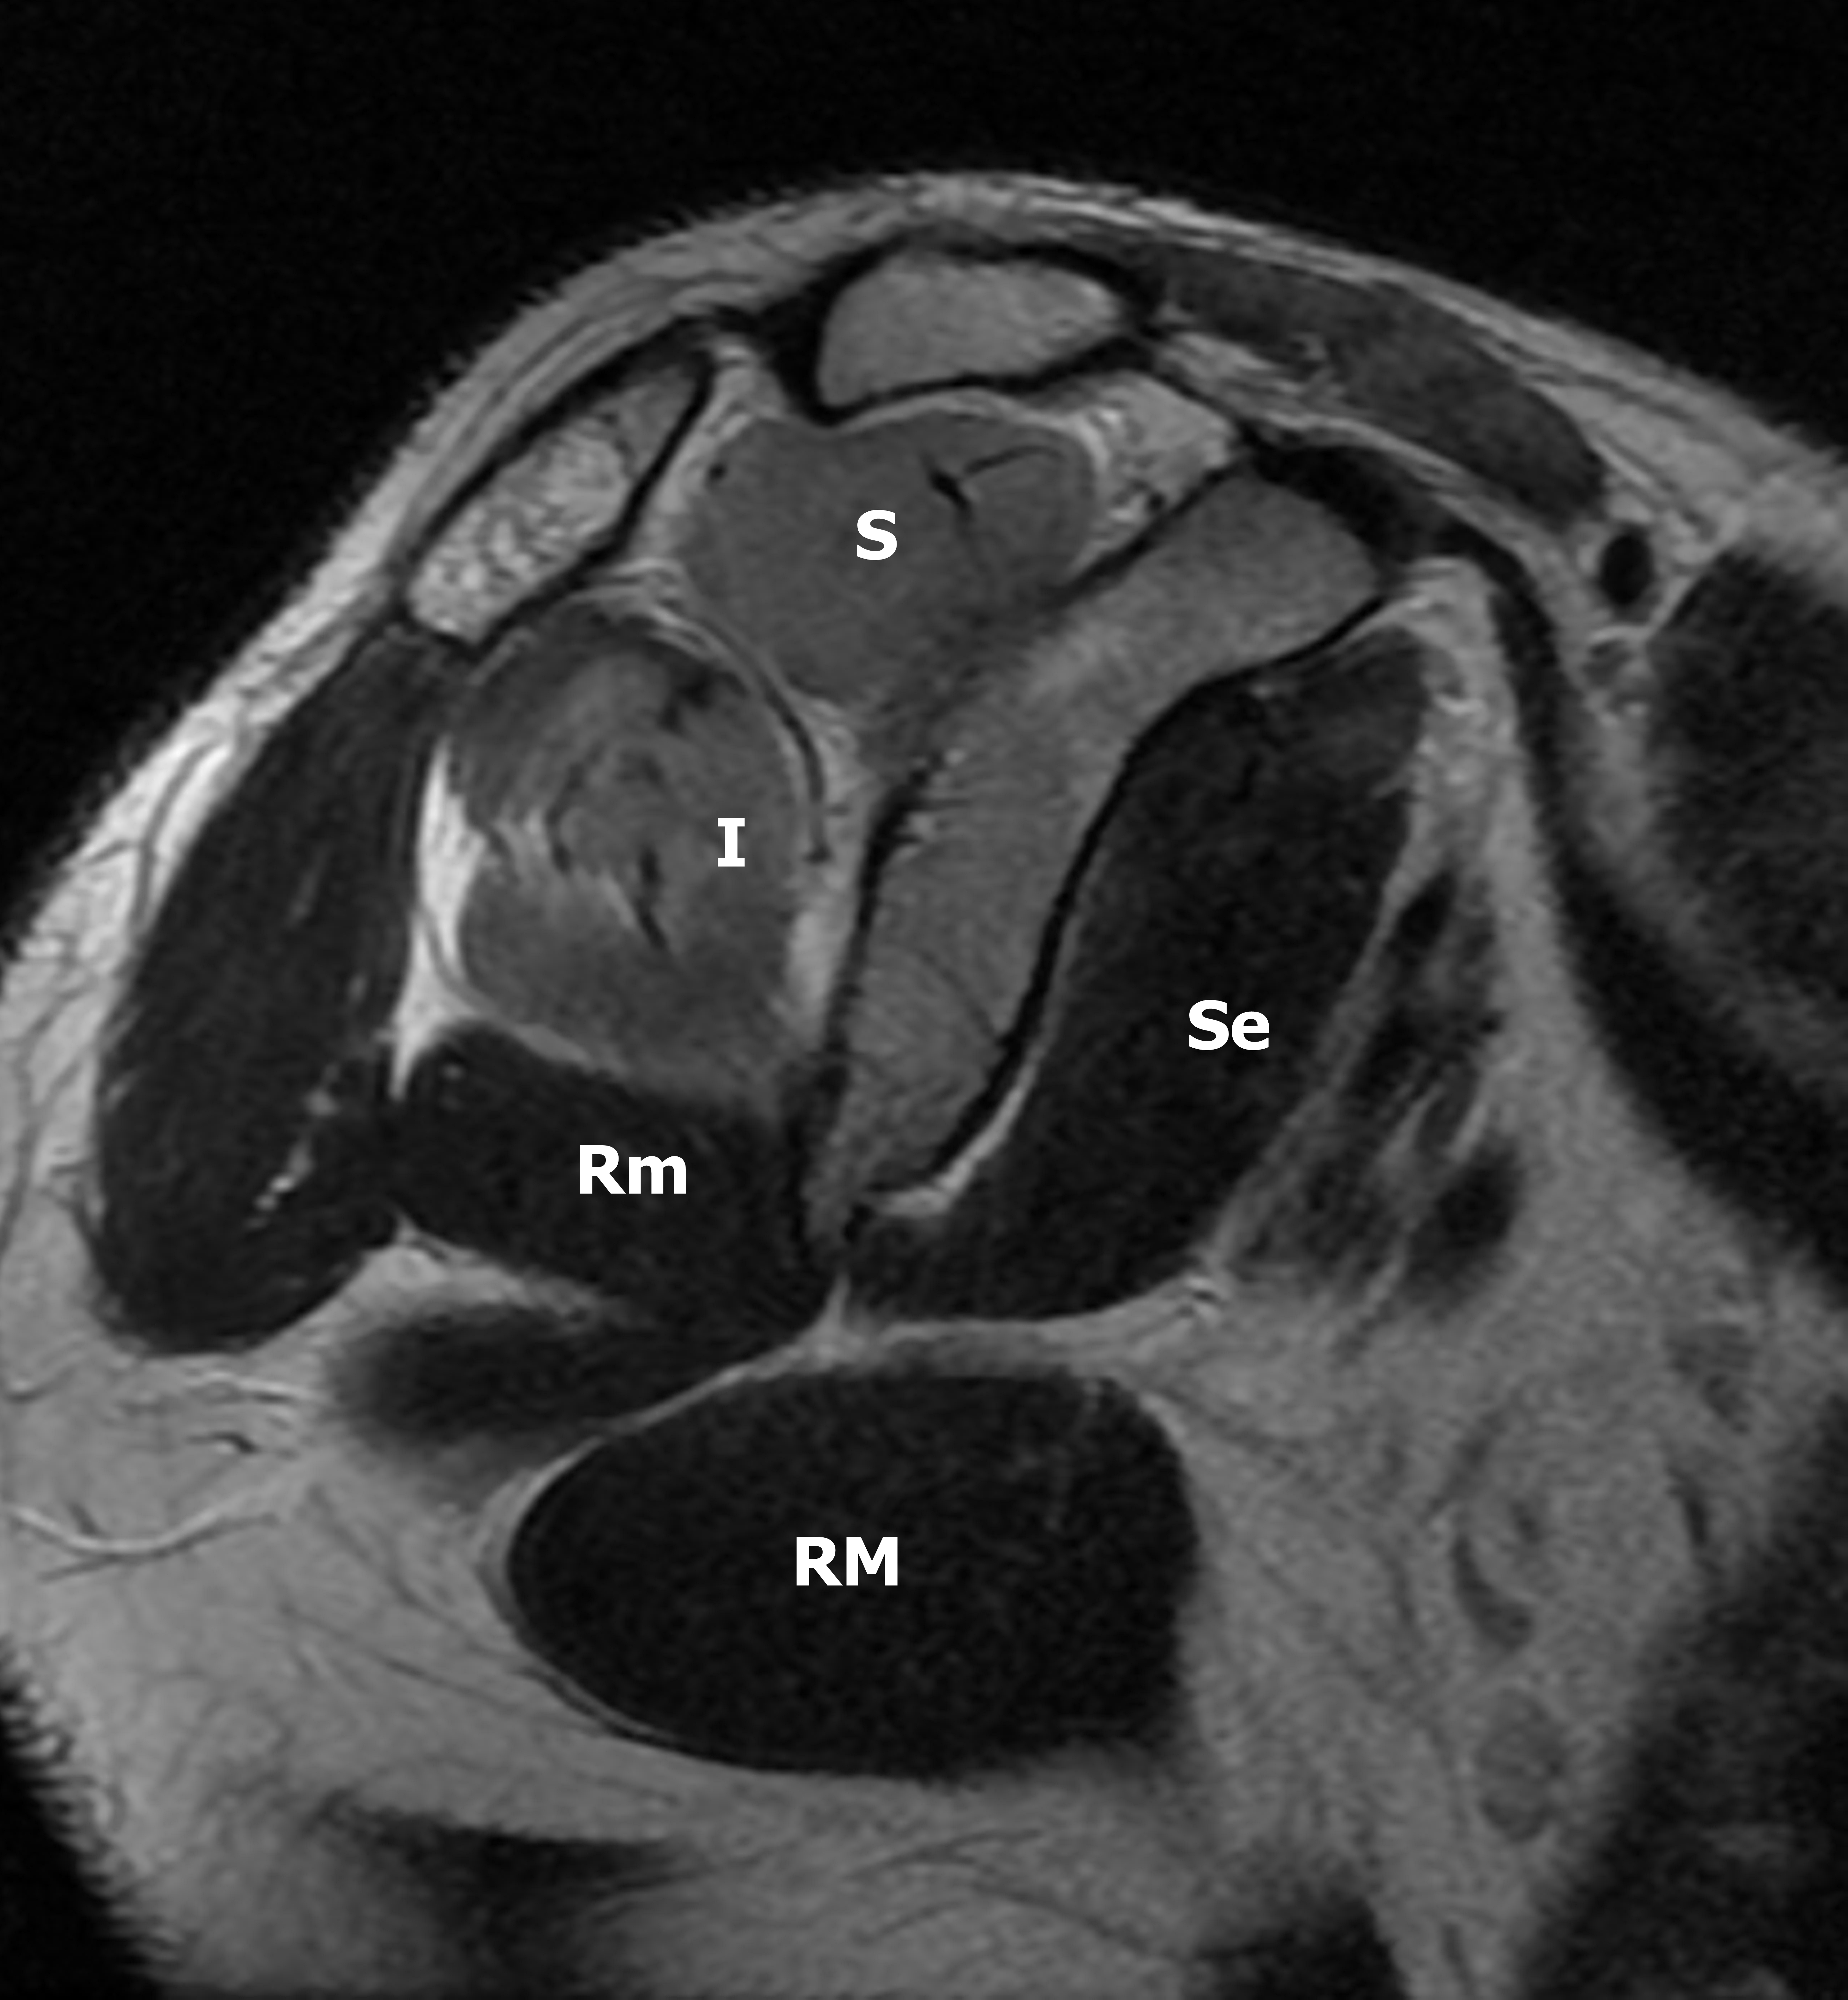

Presentación del casoMujer de 27 años de edad, con antecedentes de sepsis por estafilococo epidermidis, secundario a infección posquirúrgica de cirugía mamaria hace 3 meses, sin otros antecedentes de relevancia. Consulta en el departamento de urgencias, por presentar omalgia aguda, asociado a edema e impotencia funcional de hombro derecho, que comenzó 3 horas después de realizar actividad física intensa de CrossFit, consistente en movimientos de flexo-extensión de miembros superiores con peso.Descargas